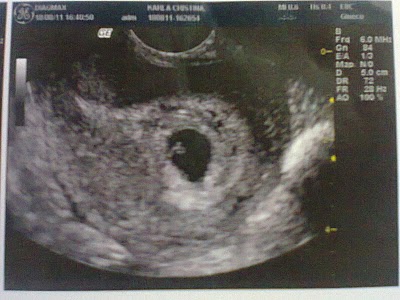

No momento estou com 7 semanas de gestação e admirada pele meu bebê estar crescendo muito rápido dentro de mim. Sempre sonhei em ter o privilégio de ser mãe ou melhor poder gerar uma pessoinha dentro de mim é uma emoção tão grande comparo com o bombardeio  de sentimentos que nem sei explicar. Sei que daqui por diante minha vida vai mudar, já mudou, tudo que faço tenho que pensar primeiro se vai fazer bem a ele, Deus é perfeito e tudo que o criou. Pude ver por dentro como seria toda formação de um bebê  e fico emocionada e grata a DEUS por saber que passarei por todo esse processo, só pedimos que venha com saúde.